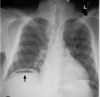

2 - chest X-ray

• can often see pleural effusion, air in mediastinum or subcutaneous emphysema

2 - chest X-ray or CT with contrast

• water soluble iodine